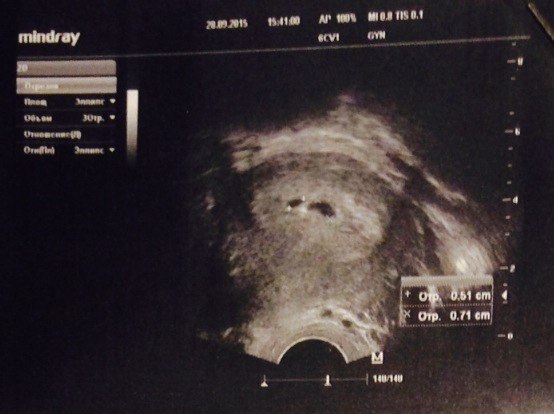

21 дпп узи

21 дпп узи 118 фото